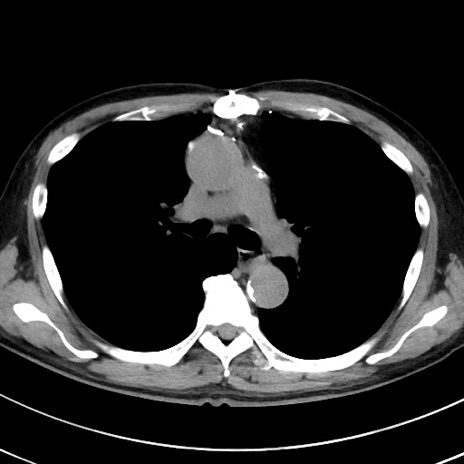

症例38(横断像)

【症例】70歳代 男性

【主訴】腹痛・嘔吐

【現病歴】昨晩より、嘔吐・腹痛あり。今朝になっても嘔吐あり。来院。

【既往歴】心臓バイパス手術、開腹胆摘、腸閉塞

【身体所見】BP 107/71mmHg、HR 116/min、腹部:平坦、軟、下腹部に軽度圧痛あり。反跳痛なし。

【データ】WBC 15100、CRP 0.32